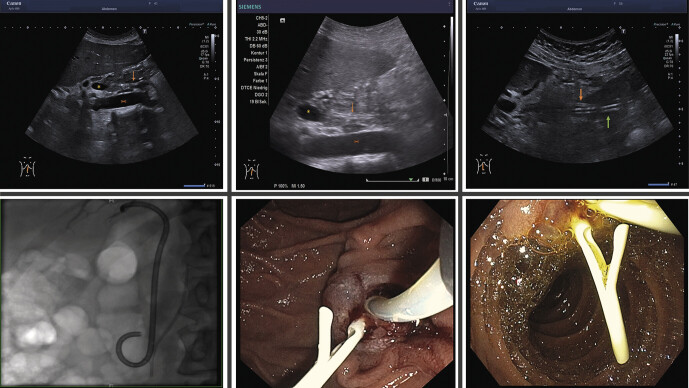

Before removal of retained pancreatic stents placed during endoscopic retrograde cholangiopancreatography to avoid post-ERCP pancreatitis, imaging is recommended. The aim of the present study was to evaluate a new ultrasound-based algorithm.Patients who received a pancreatic stent for PEP prophylaxis were included. Straight 5Fr (0.035inch) 6cm stents with an external flap that were visualized by ultrasound were removed endoscopically with no further imaging. If the ultrasound result reported the stent to be dislodged or was inconclusive, X-ray imaging was performed. The endpoints were positive and negative predictive value, specificity, sensitivity, and contingency coefficient between ultrasound and X-ray and/or endoscopy.88 patients were enrolled in the present study. X-ray was performed in 23 (26%) patients. Accordingly, the ultrasound algorithm saved an X-ray examination in 65 cases, leading to a reduction of 74%. Stents were retained in 67 patients (76%) and visualized correctly by ultrasound in 54 patients with a sensitivity of 81%. The positive predictive value was 83%. The specificity was 48%, because ultrasound described 10/21 dislodged stents correctly. The negative predictive value was 43%, since 10/23 stents were correctly classified by ultrasound as dislodged. In 11 patients (13%), esophagogastroduodenoscopy was performed even though the pancreatic stent was already dislodged.A novel ultrasound-based algorithm reduced the need for X-ray imaging by three quarters. To avoid unnecessary endoscopic examinations, the algorithm should be implemented with a learning phase and procedures should be performed by experienced examiners. An important limitation might be stent length since shorter stents might be more difficult to visualize by ultrasound.

目的:在内镜逆行胰胆管造影术中放置了胰腺支架,为避免ERCP术后胰腺炎,建议在取出残留的胰腺支架前进行造影。本研究旨在评估一种基于超声波的新算法。材料和方法:纳入接受胰腺支架以预防 PEP 的患者。在内镜下取出经超声检查可见的带有外瓣的 5Fr(0.035 英寸)6 厘米直支架,不再进行进一步的造影检查。如果超声结果显示支架移位或无法确定,则进行 X 光成像。研究终点为阳性和阴性预测值、特异性、敏感性以及超声与 X 光和/或内窥镜之间的或然系数。有 23 名患者(26%)接受了 X 光检查。因此,超声算法节省了 65 例 X 光检查,减少了 74%。67名患者(76%)保留了支架,54名患者的超声检查结果正确,灵敏度为81%。阳性预测值为 83%。特异性为 48%,因为超声正确描述了 10/21 个移位的支架。阴性预测值为 43%,因为有 10/23 个支架被超声正确归类为移位。有 11 名患者(13%)即使胰腺支架已经移位,仍需进行食管胃十二指肠镜检查。为避免不必要的内镜检查,该算法在实施过程中应有一个学习阶段,且手术应由经验丰富的检查人员进行。一个重要的限制因素可能是支架的长度,因为较短的支架可能更难通过超声显像。__________________ 背景:目前建议在内镜逆行胰胆管造影术后取出预防性放置的胰腺支架前进行成像。本研究旨在评估一种基于超声波的新算法。材料和方法:纳入接受预防性胰腺支架植入术的患者。只需在内镜下取出距外法兰 6 厘米长的 5 Fr 支架(0.035 英寸),超声检查可见,无需进一步成像。如果超声结果显示支架移位,则进行 X 光检查。研究终点为阳性和阴性预测值、特异性、敏感性以及超声与 X 光和/或内窥镜检查之间的或然系数。结果:88 名患者被纳入研究。23名患者(26%)必须进行X光检查。因此,在 65 例患者(74%)中,超声波算法节省了 X 光检查。67名患者(76%)保留了支架,54名患者的超声检查结果正确,灵敏度为81%。阳性预测值为 83%。特异性为 48%,因为超声正确显示了 10/21 个脱位的支架。阴性预测值为 43%,因为有 10/23 个支架被正确归类为脱位。虽然胰腺支架已经脱位,但仍有 11 名患者(13%)进行了食管胃十二指肠镜检查。结论:基于超声波的算法将 X 光成像的需求减少了四分之三。为避免不必要的内镜检查,该算法在实施过程中应有一个学习阶段,且手术应由经验丰富的检查人员进行。一个重要的限制因素可能是支架的长度,因为较短的支架可能更难以用超声波观察到。